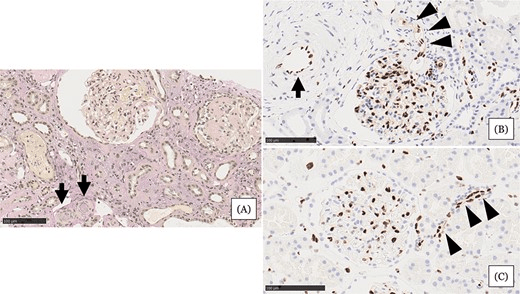

• 腎活檢示小動(dòng)脈嚴(yán)重狹窄或阻塞,內(nèi)皮損害嚴(yán)重,腎小球萎縮,間質(zhì)細(xì)胞浸潤(rùn)(圖1A)

• 與血壓正常的正常腎組織相比,血管內(nèi)皮細(xì)胞(EC)細(xì)胞核等長(zhǎng)排列整齊(圖1C)

• 患者腎組織中EC細(xì)胞核大小不一,細(xì)胞核明顯,小動(dòng)脈內(nèi)細(xì)胞核較少(圖1B)

綜合以上表現(xiàn),診斷該患者急性腎損傷類型為難治性高血壓合并微血管病性溶血導(dǎo)致的急性慢性缺血性腎損害。

圖1:住院第 31 天的腎臟活檢結(jié)果。